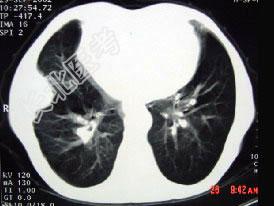

- 单项选择题CT图像,最可能诊断为 ( )

A、右肺肺占位

B、右侧胸膜良性病变

C、肋骨病变侵犯胸壁

D、膈膨升

E、纵隔肿块